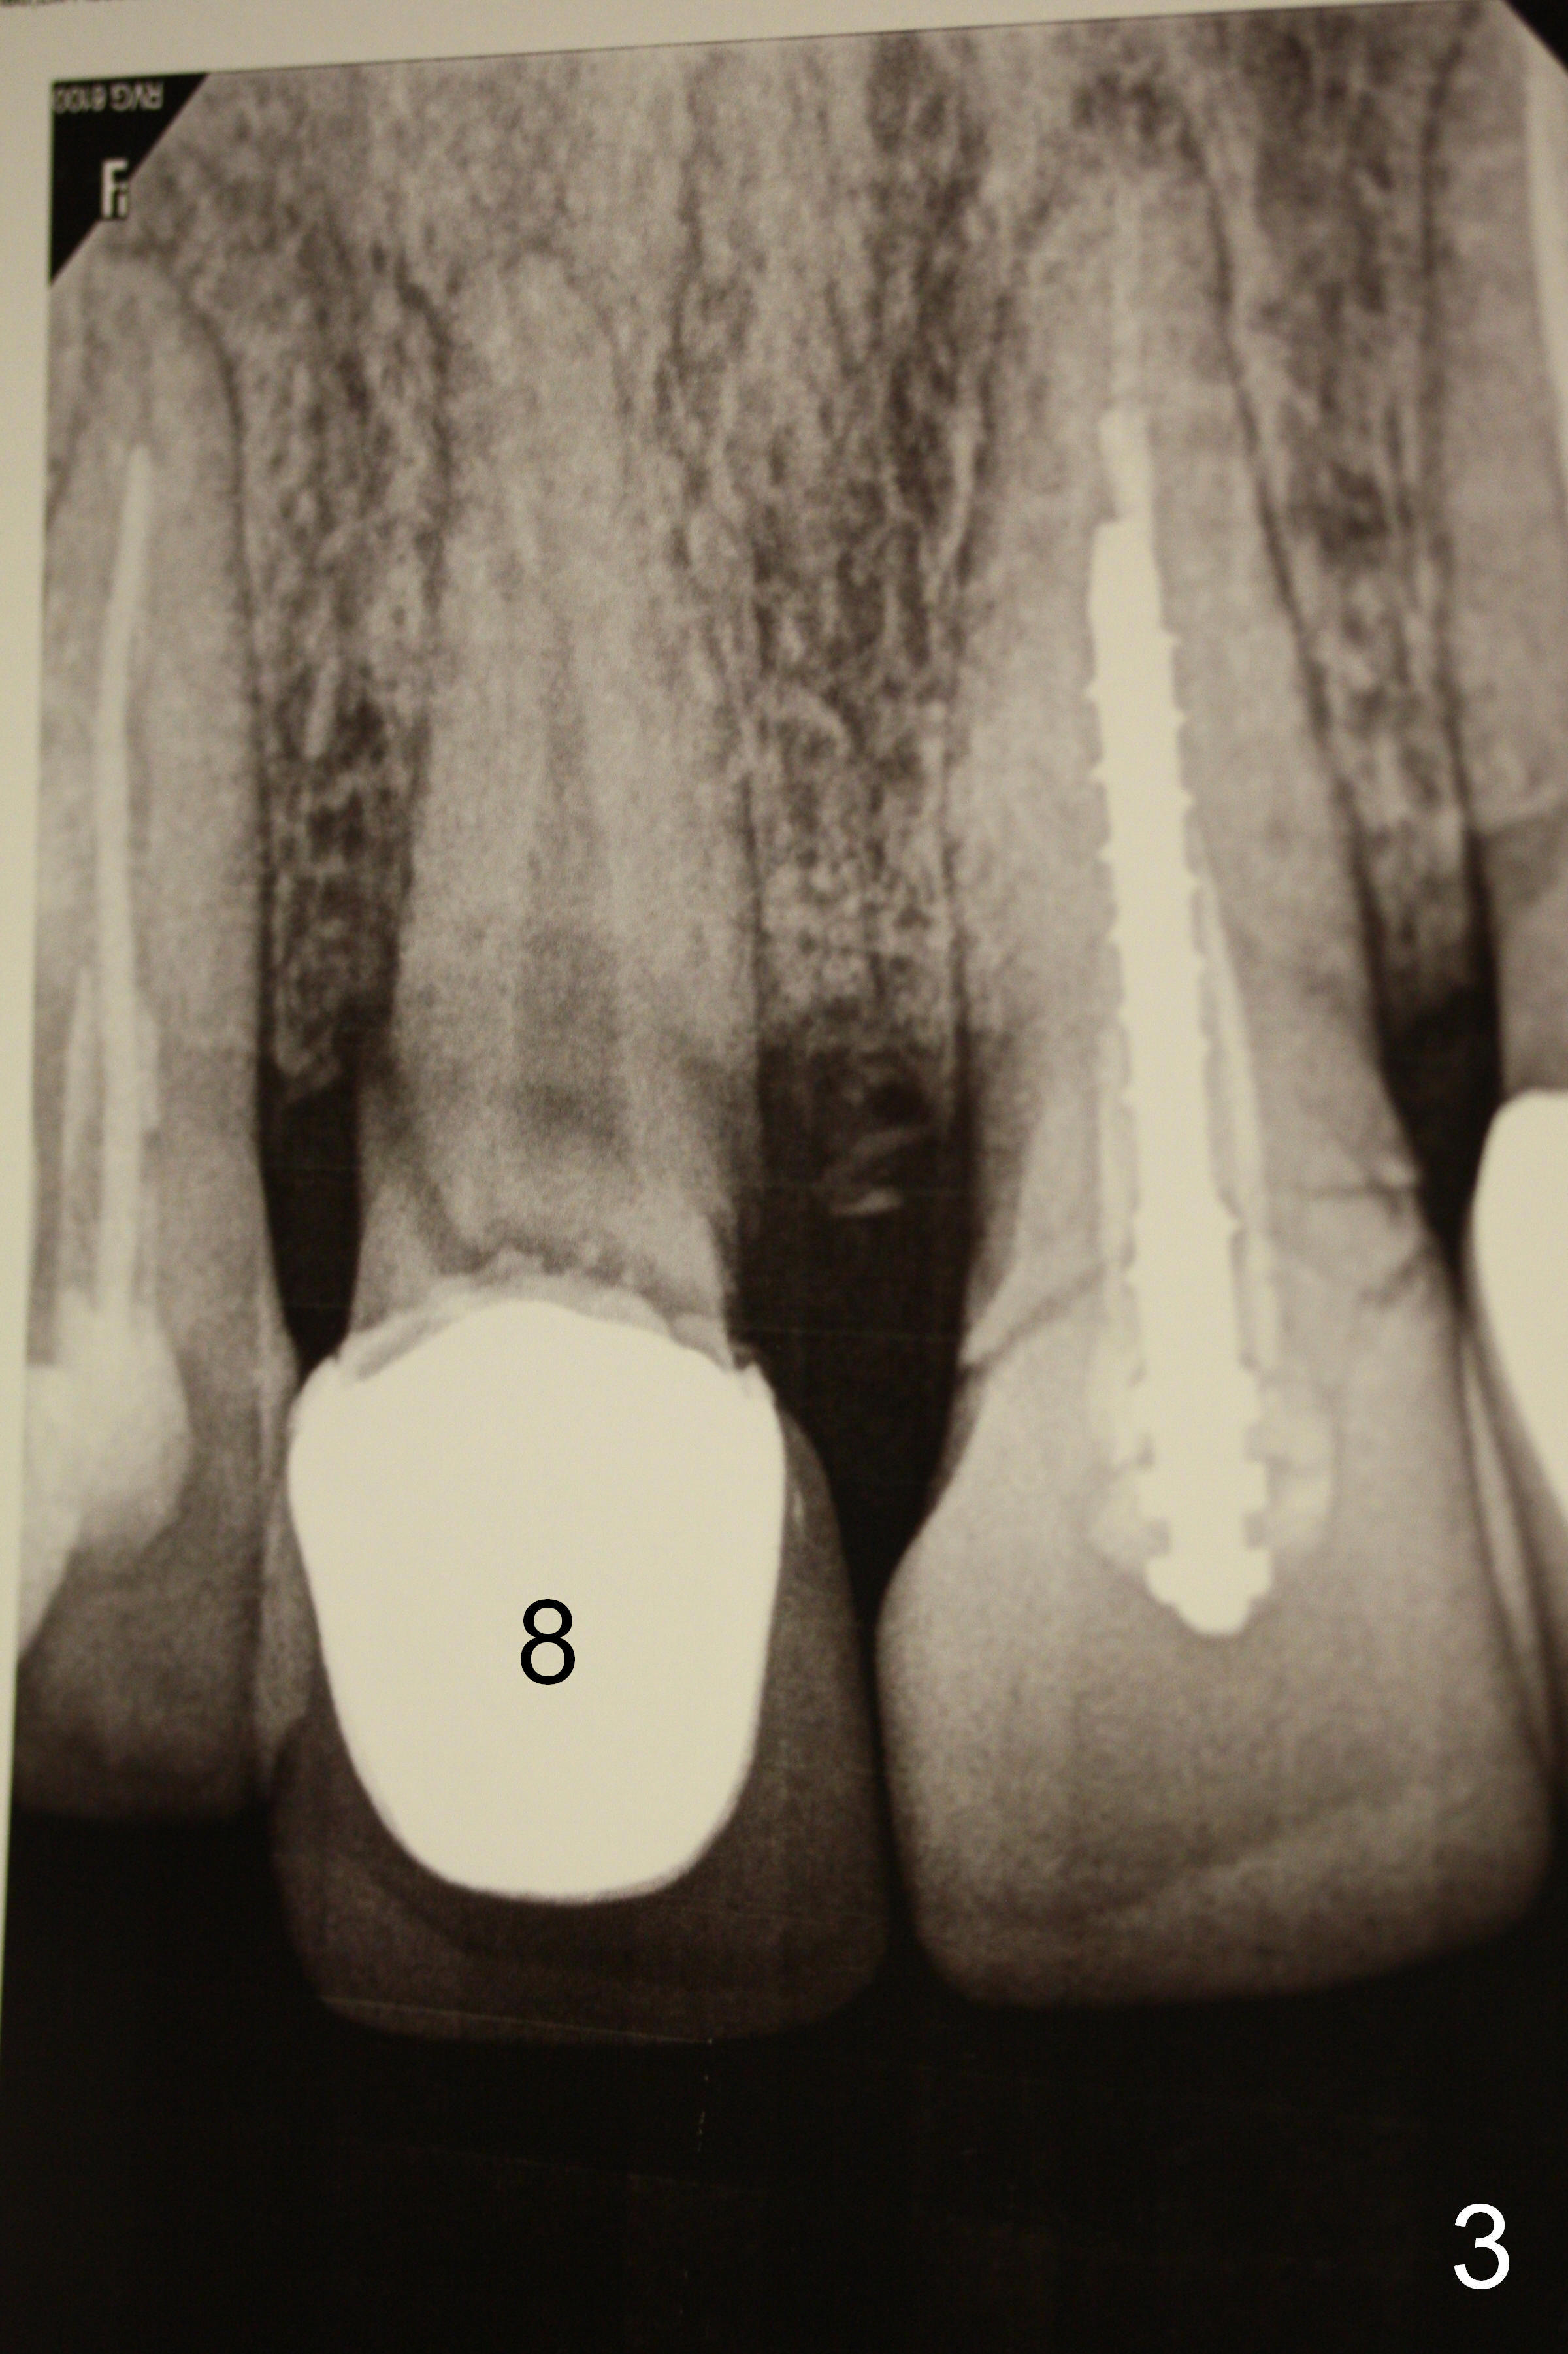

A 40-year-old lady has multiple restorations (Fig.1). Two of them require implants (#4 (Fig.2, severe caries) and #8 (Fig.3, root fracture). The root of #4 is long and curved (Fig.2). It may present a challenge to extraction, but not implant placement. The narrow and long root is favorable to primary stability. A 2 mm pilot drill is used to initiate osteotomy in the palatal wall of the socket, followed by 2.5 and 3 mm reamers at 17 mm (gingival level). If the bone is soft, the depth for the 3 mm reamer will be reduced to 14 mm. A 4.5x20 mm Tatum tapered tap will be used at 17 mm deep to test stability.